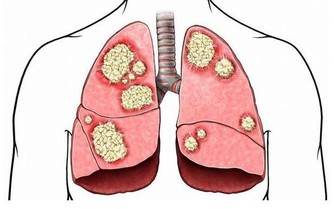

長年熬夜的人,無論男女,直接傷肝,日久傷腎,逐步造成身體氣血雙虧,每天照鏡子時會覺得臉色灰土一片。